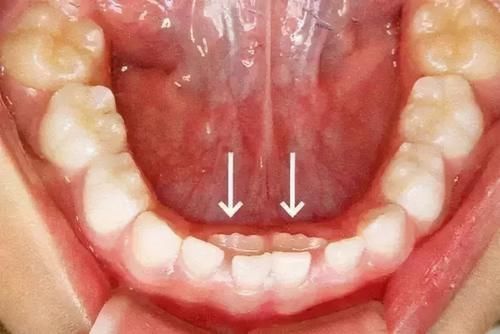

发现堆堆所指向的位置的侧边生长出来了牙齿,这可把堆堆的妈妈吓坏了。

因为堆堆妈妈之前看到过,有些孩子因为某些不良的原因,可能会导致出现“双排牙”的情况。

3)恒牙生长位不对

如果孩子的恒牙生长位置不正,恒牙在生长的时候,无法正常的刺激乳牙的根部,那么乳牙的牙根就不会产生相应的生理吸收反应。

而很显然,乳牙的牙根依旧坚挺,导致乳牙迟迟不掉,而恒牙则有可能从其它位置萌生出来,更有甚者还可能会因为萌生位的不对而造成局部的牙齿疾病等。